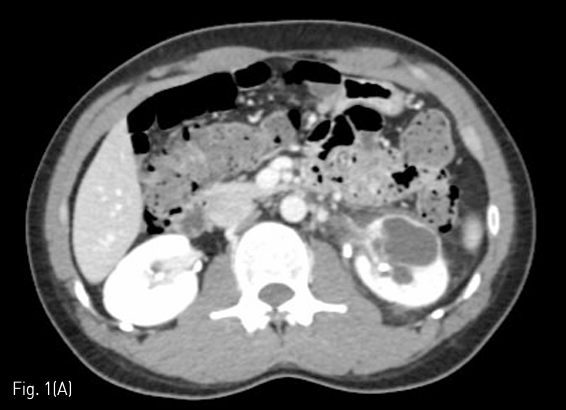

조영증강 전산화 단층촬영에서 왼쪽 신장의 아래쪽에 약 3.5cm 크기의 낭성 병변이 왼쪽 신장에 있었다. 내부에 조영증강의 소견이나 격벽은 없었으며 CT number는 0-15로 측정되었다. (Fig. 1A)

Fig 1A

(A) Nephrographic phase of contrast enhanced CT showed a 3.5cm sized cystic lesion in left kidney lower pole.